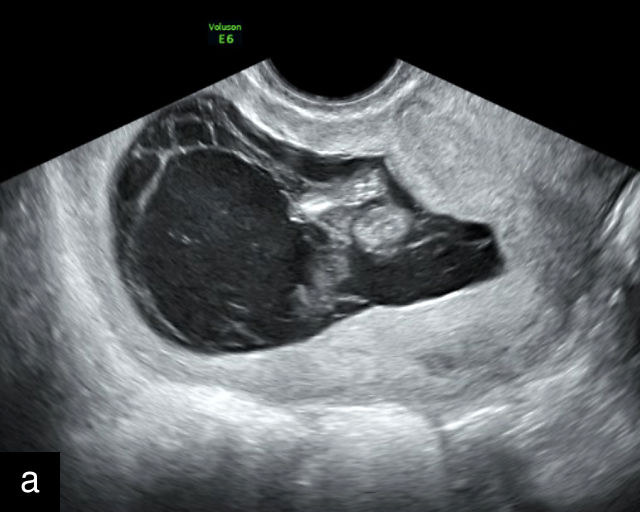

In the early first trimester, trophoblastic tissue appears as an echogenic ring encircling the gestational sac (Figure 1a). By the late first trimester, the placenta becomes recognizable as a distinct structure on ultrasound (Figure 1b). Initially, it presents as a homogeneous echogenic mass (Figure 1b–d) but undergoes progressive differentiation, becoming more heterogeneous as pregnancy advances from the second to third trimester (Figure 1e–g). By the third trimester, cotyledons become discernible, and in the late third trimester, calcifications frequently appear basally and around the cotyledons (Figure 1g).

1

Ultrasound images of development of the placenta (P/p). (a) Trophoblastic tissue appearing as an echogenic ring surrounding the gestational sac at 6 weeks' gestation. (b) Placenta at 12 weeks has become a discrete, uniformly echogenic mass. (c) Placenta at 17 weeks. (d) Placenta at 20 weeks. (e) Placenta at 27 weeks. (f) Placenta at 33 weeks. Increasingly, differentiation and heterogeneous appearance is seen, with demarcation of the cotyledons. Basal calcifications are beginning to appear. (g) Placenta at 40 weeks, showing a distinctly heterogeneous appearance, with clear demarcation of the cotyledons and presence of calcifications.